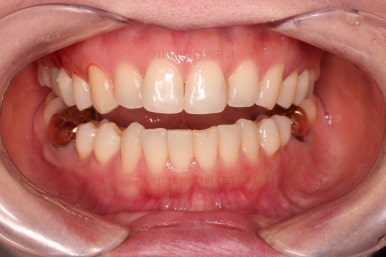

마찬가지로 부산치아교정비용 초진 시 입안의 모습입니다.

아랫니가 많이 보이지 않는 타입이라서 잘 몰랐는데 입안을 관찰해 보니 아래 앞니가 삐뚤어 있네요.

이 부분도 꼭 교정해야 될 정도는 아니여서 선택의 문제라고 할 수 있는데요.

치료 종료시의 모습인데요.

임플란트가 잘 들어갔고 아래 앞니도 원하는 모습으로 잘 배열이 되었습니다.

부산치아교정비용 전후 비교해 볼게요.